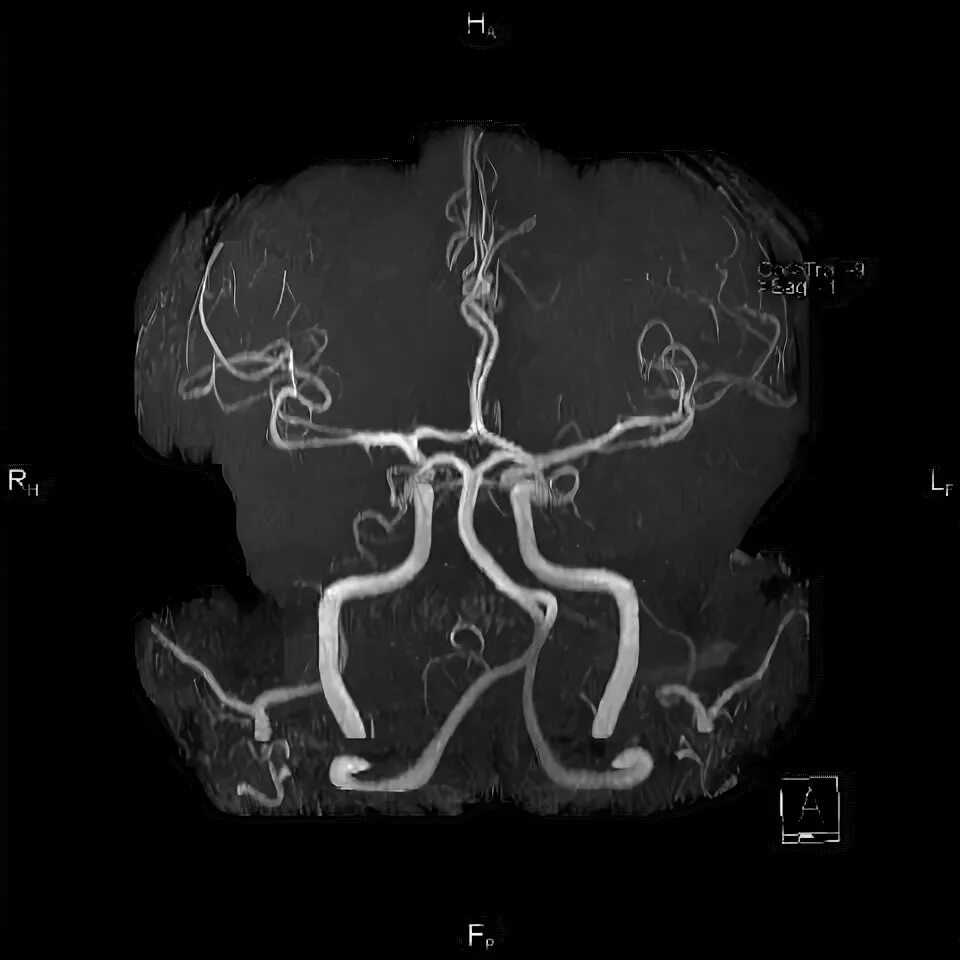

Мрт сосудов головного мозга в туле